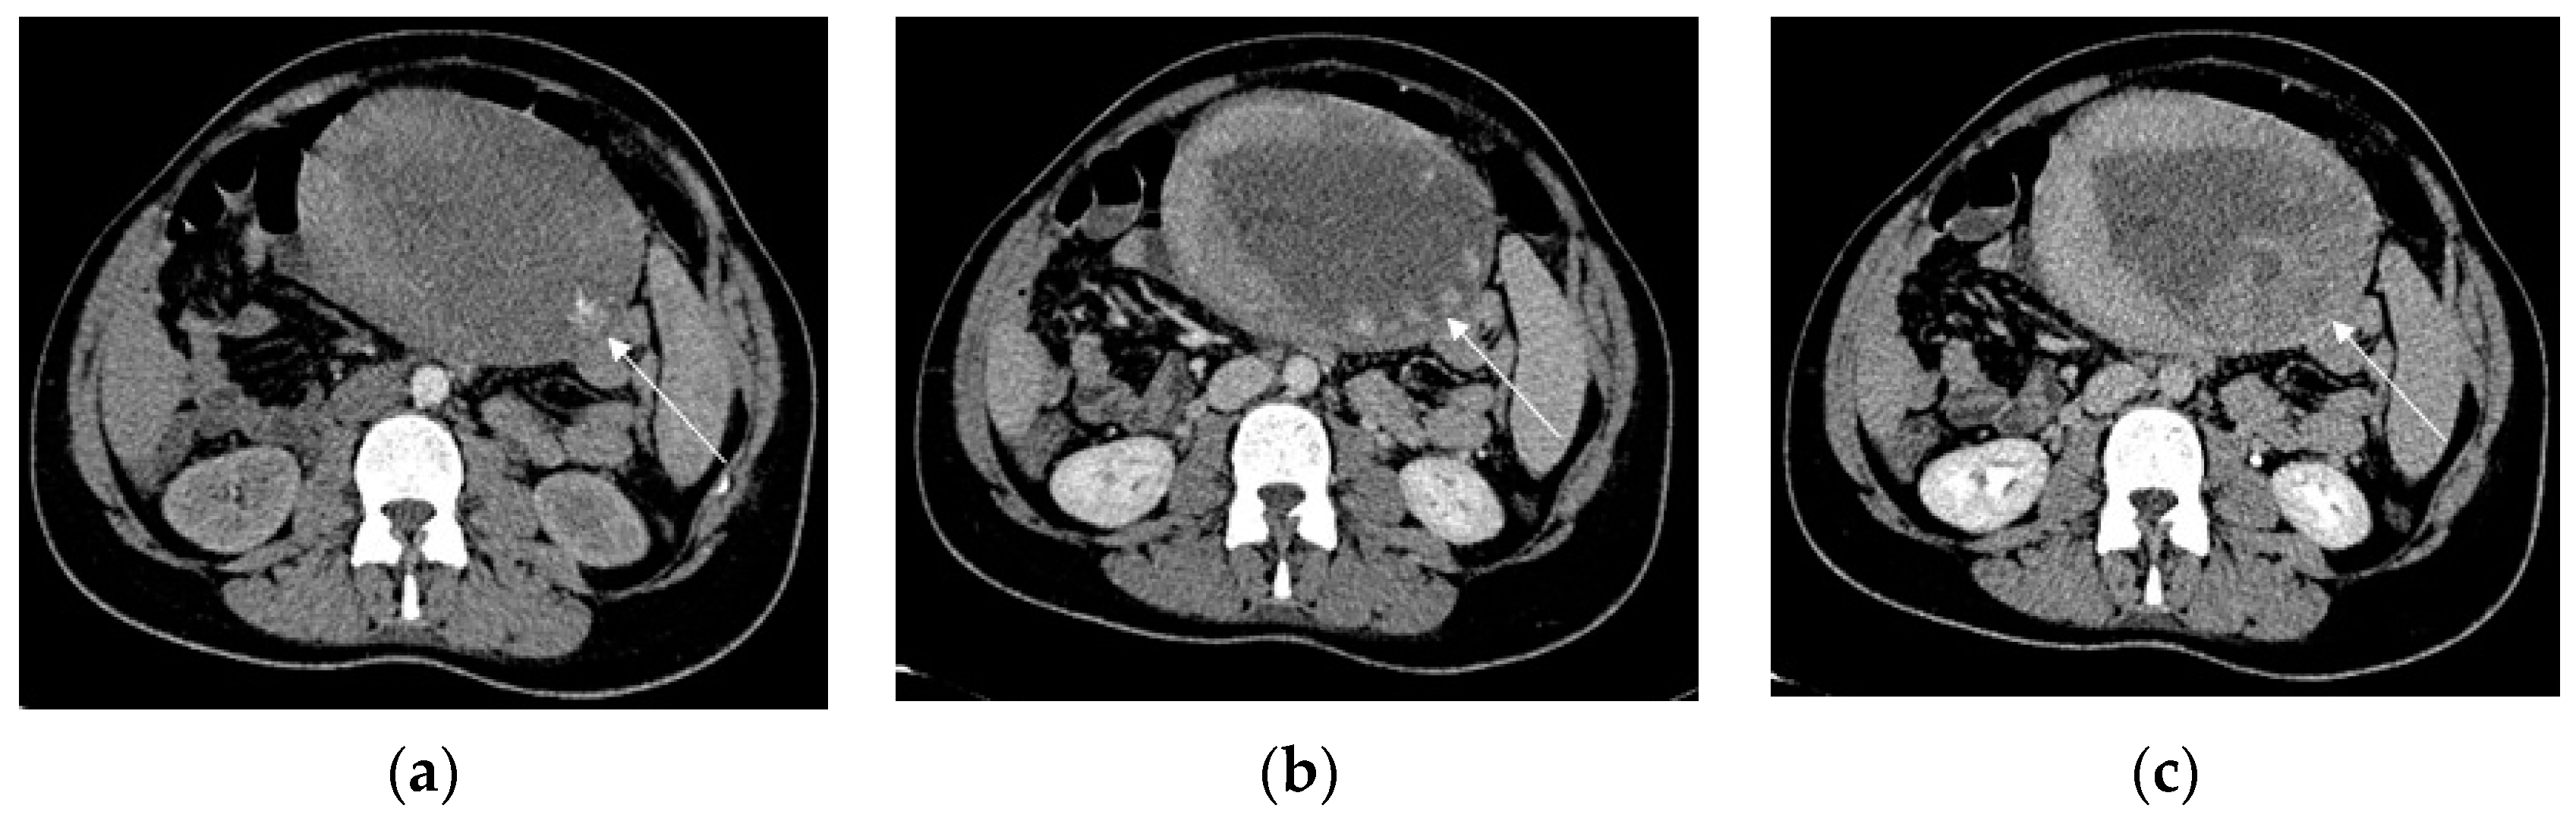

Contrast-enhanced CT should be performed to detect and localize active bleeding that appears as extravasation of the contrast agent. Significant arterial bleeding can be identified on the arterial phase, while small arterial or venous oozing can be detected during the delayed phase (Figure 8) [97].

Figure 8. Primary postpartum hemorrhage occurring 6 h after delivery, in a 28-year-old patient with previously undiagnosed PAS disorder. Axial early arterial phase (a) contrast-enhanced CT scans demonstrate a subtle intrauterine contrast extravasation (arrow) in the left side of the endometrial cavity. The contrast extravasation is clearly depicted in the portal phase (b), whereas the delayed phase (c) demonstrates a more diffuse contrast extravasation in the same side.